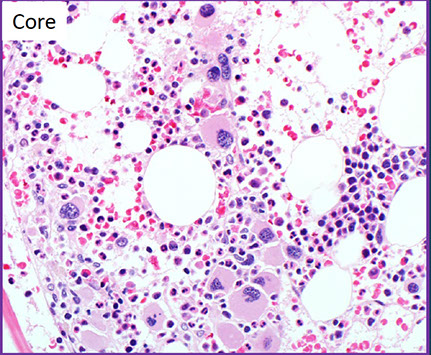

BM findings

Usually hypercellular marrow for age with erythroid hyperplasia, but may see normocellular or hypocellular marrow

Generally increased number of blasts

Generally trilineage dysplasia (dyshematopoiesis)

- Abnormal localization of immature myeloid precursors (ALIP)